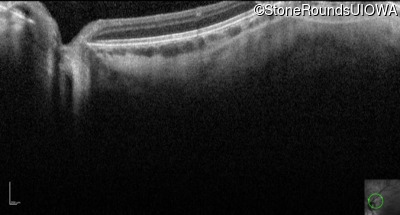

Optical Coherence Tomography - Right - 10/160 +1 sc

Exemplar / OCT Stack

OCT Stack

Optical Coherence Tomography - Left - 10/200 sc